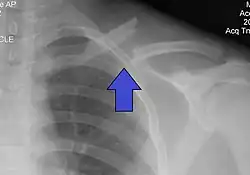

| X-ray of a left clavicle fracture | |

It is often caused by a fall onto a shoulder, outstretched arm, or direct trauma.[1][3] The fracture can also occur in a baby during childbirth.[1] The middle section of the clavicle is most often involved.[3] Diagnosis is typically based on symptoms and confirmed with X-rays.[2]

The basic method to check for a clavicle fracture is by an X-ray of the clavicle to determine the fracture type and extent of injury. In former times, X-rays were taken of both clavicle bones for comparison purposes. Due to the curved shape in a tilted plane X-rays are typically oriented with ~15° upwards facing tilt from the front. In more severe cases, a computerized tomography (CT) or magnetic resonance imaging (MRI) scan is taken. However, the standard method of diagnosis through ultrasound imaging performed in the emergency room may be equally accurate in children.[6]